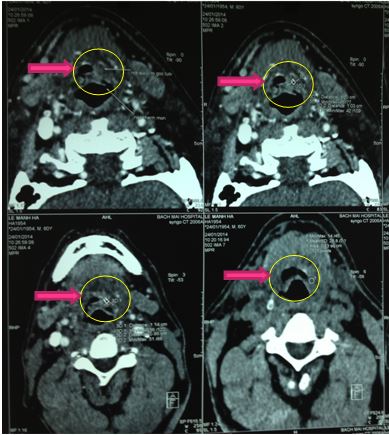

Chụp cắt lớp vi tính 64 dãy vùng hầu họng:

+ Khối sùi vị trí đáy lưỡi thanh thiệt kích thước 32x24mm, bờ không đều, ranh giới không rõ, tỷ trọng mô mềm, ngấm thuốc mạnh sau tiêm (46-83HU), khối dính một phần vào sụn nắp thanh môn, lồi vào lòng thanh quản gây hẹp lòng thanh quản, vị trí hẹp nhất 4mm, chưa phát triển xâm lấn vào xoang lê hai bên.

+ Hạch to vùng cổ hai bên dọc bó mạch cảnh, khối hạch lớn nhất bên phải 20x12mm, bên trái 26x17mm, hạch ngấm thuốc mạnh sau tiêm

Kết luận: Hình ảnh khối u sùi vị trí hố đáy lưỡi thanh thiệt, hạch to vùng cổ hai bên.

Hình 2. Hình ảnh khối u trên hình ảnh cắt lớp vi tính 64 dãy vùng hầu họng